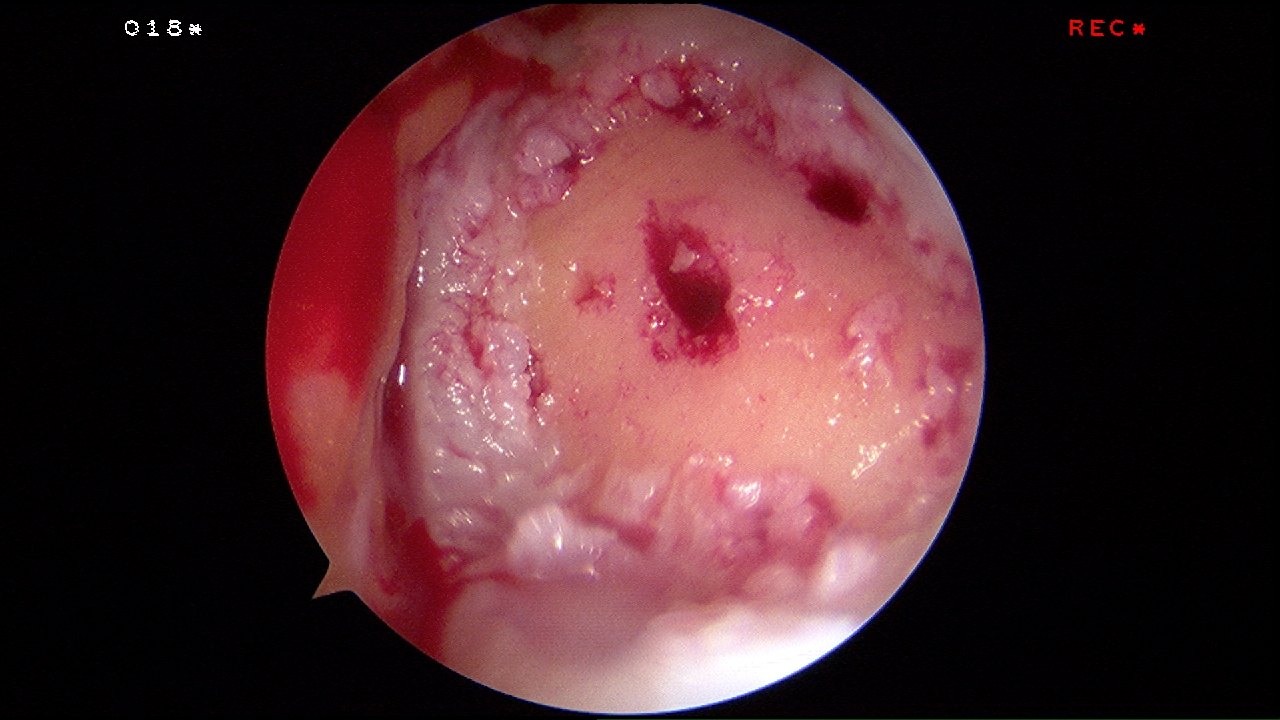

Hyalofast acts as a scaffold for bone marrow aspirate or as a chondroprotective coverage which allows in situ residence of mesenchymal stem cells and other autologus bone marrow elements after their mobilization due to microfracture or perforation procedures. Upon degradation, the HYAFF based scaffold releases natural hyaluronic acid.

Hyalofast can be applied arthroscopically, it is easily conformable and its adhesive nature allows non mechanical fixation in most cases. It is intrinsically safe as it is composed of pure HA derived from a non-animal source.

The hyalofast scaffold is cut to the right side, mixed with blood and inserted over the cartilage defect arthroscopically.